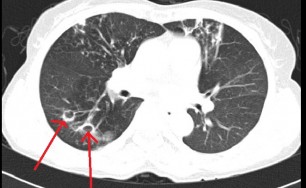

숨케어한의원에서는 전화예약을 받고 있습니다. 내원시 엑스레이, CT사진, 폐기능검사지를 가지고 오시면 자세한 상담이 가능합니다.